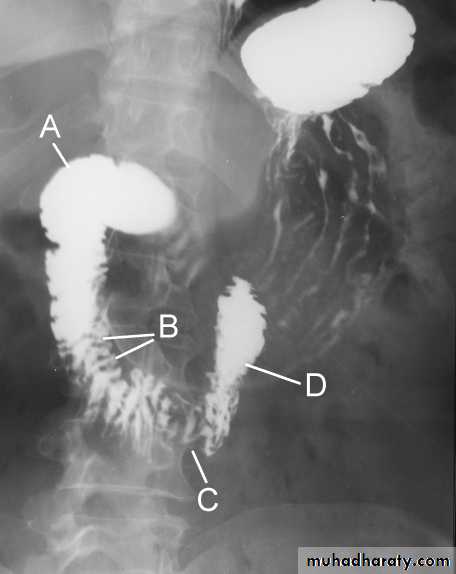

Barium meal Fluoroscopy + spot films Preparation

The Normal Anatomy of Stomach1- Shape.2-Size.3-Site.4-Anatomical parts.5-Mucosal pattern.

Normal Anatomy of DuodenumDuodenal cap.Duodenal loop